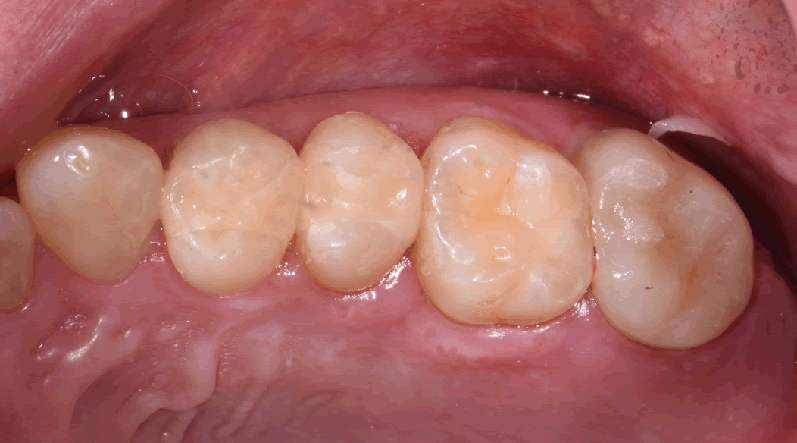

Visual examination revealed decay on the mesial marginal ridge and distal marginal ridge of tooth #13 as well as extensive buccal and occlusal decay on tooth #15 (Figs. 1-2). Bitewing radiographs and intraoral photographs were taken, which confirmed the above diagnosis and also exposed additional decay on the distal of tooth #12 (Figs. 3-4).

Figs. 1 and 2

Inlays and crown were prepped, and the rubber dam was removed for photos (Figs. 8-9).

Fig. 8 Fig. 9